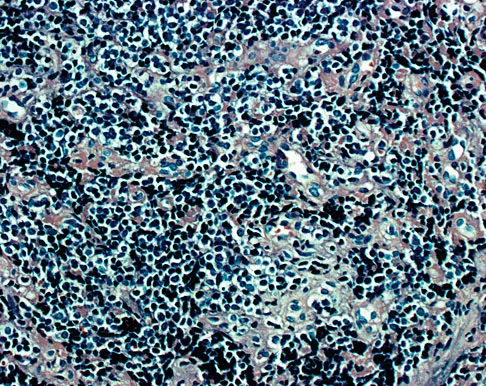

Figures 1a through 1c show the radiograph and MRI scans of a 16-year-old patient who has a painful hip. Examination reveals a significant limp, limited abduction and internal rotation, and severe pain with internal rotation and adduction. A biopsy specimen is shown in Figure 1d. What is the deposited pigment observed in this condition?

Explanation

Pigmented villonodular synovitis (PVNS) is a synovial proliferative disorder that remains a diagnostic difficulty. The most common clinical features are mechanical pain and limited joint motion. On radiographs, the classic finding is often a large lesion, associated with multiple lucencies. Other findings may include a normal radiographic appearance, loss of joint space, osteonecrosis of the femoral head, or acetabular protrusion. MRI is the imaging modality of choice and will show the characteristic findings of a joint effusion, synovial proliferation, and bulging of the hip. The synovial lining has a low signal on T1- and T2-weighted images, secondary to hemosiderin deposition. Copper deposition occurs in patients with Wilson's disease, which mainly affects the liver. Bhimani MA, Wenz JF, Frassica FJ: Pigmented villonodular synovitis: Keys to early diagnosis. Clin Orthop 2001;386:197-202.